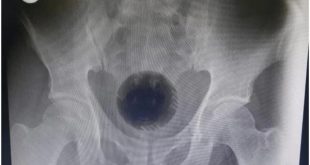

Homem passa por cirurgia para tirar bola de sinuca do ânus

Ele chegou com vergonha no hospital alegando que havia tentado uma nova forma de tratar suas hemorroidas Um homem de 51 anos precisou passar por uma cirurgia para retirar uma bola do ânus. O caso aconteceu em Irbid, uma cidade da Jordânia.  Segundo informações do “Daily Mail”, o homem chegou ...